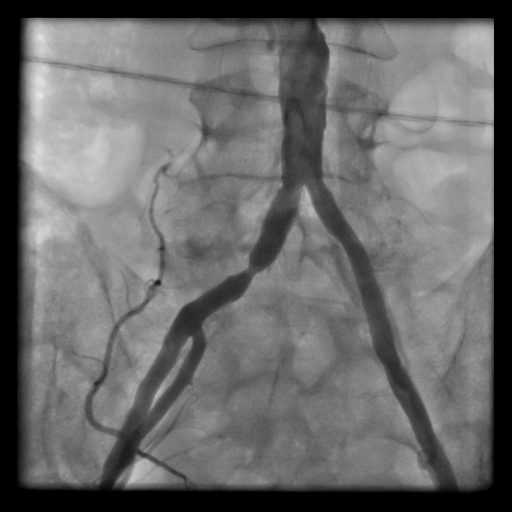

Damar sertliği hastalığı koroner arterler gibi kol, karın ve ayaklardaki damarlarda da tıkanmalara yol açar ve kendini özellikleyürüyüş anında veya kol hareketlerinde ağrı ile gösterir. İlerleyen aşamalarda ağrıya, enfeksiyon ve iyileşmeyen yaralar eşlik edebilir hatta ampütasyona (“ayak kesilmesi”) kadar ilerleyebilir. Yaşlılarda karın damarlarında gelişen tıkanıklıklar cinsel güç kaybına yol açabilir. Anjiografi ile darlığın yeri saptandıktan sonra, balonla genişletilerek stentlenir ve damar açılır, neticede bu darlığın yol açtığı istenmeyen durum ve şikayetlerde kaybolur.Anjiografi laboratuvarında lokal anestezi altında yapılan bir işlemdir.

- Aort Damar Hastalıklarında Endovasküler (stentleme) Tedavisi (EVAR)